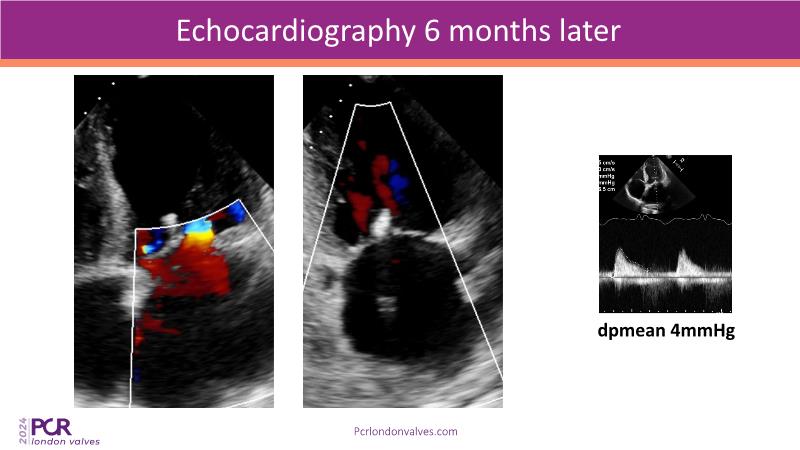

This session examines two compelling cases: a 78-year-old woman with paroxysmal atrial fibrillation, chest trauma, an osteoporotic sternum fracture, and NYHA II exertional dyspnoea, and an 82-year-old man with chronic three-vessel coronary artery disease, bradycardic AF, peripheral arterial disease, spinal stenosis, and chronic kidney disease. Through their study, discover the intricate anatomy of atrioventricular valves, the therapeutic challenges they pose, and the growing significance of transcatheter edge-to-edge repair (TEER) therapies. The discussion also highlights the value of multidisciplinary strategies in managing complex valve diseases effectively.